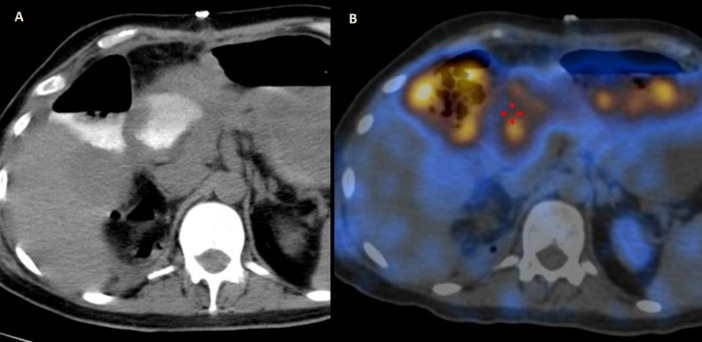

Perforation of the bowel can be a life-threatening condition and is usually clinically diagnosed when a patient presents with such features as severe abdominal pain, tenderness, and tachycardia. Bowel perforation may be corroborated by various conventional imaging modalities, including X-ray, ultrasonography, computed tomography, and magnetic resonance imaging. Nuclear medicine imaging modalities seldom have a role to play in these settings. Rarely diagnosis of perforation may be missed if it is concealed and does not present with the usual signs. Mostly the perforation will eventually be diagnosed if they develop signs and symptoms and is taken up for an exploratory laparotomy. A delay in diagnosis can later lead to significant patient morbidity or even mortality. This report describes a case where possible intestinal perforation was suspected on a 99mTc-DTPA renogram in a postoperative patient with significant urine leak, the presence of which was confirmed intraoperatively. To our knowledge, this was the first such case in the literature.